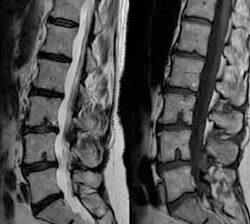

É uma distensão do anel fibroso que envolve os discos intervertebrais. Tal distensão ocorre sem rompimento do anel fibroso que envolve o disco. O núcleo discal “empurra” o anel causando seu desgaste e dilatação, o que faz com que os ligamentos e outras estruturas localizadas ao redor do disco com protusão sejam atingidos e causem dor na região. Esta característica é a principal diferença entre protusão e hérnia discal.

A degeneração discal é um processo evolutivo natural, o disco intervertebral desidrata com o envelhecimento, de forma progressiva, e não necessariamente esta associado a sintomas dolorosos.

Hérnia de disco é a ruptura do ânulo fibroso (estrutura externa do disco intervertebral), com projeção da sua parte interna, para fora, levando a compressão de nervos.

Herniações intrassomáticas benignas localizadas nos platôs vertebrais, na maioria das vezes são assintomáticas.